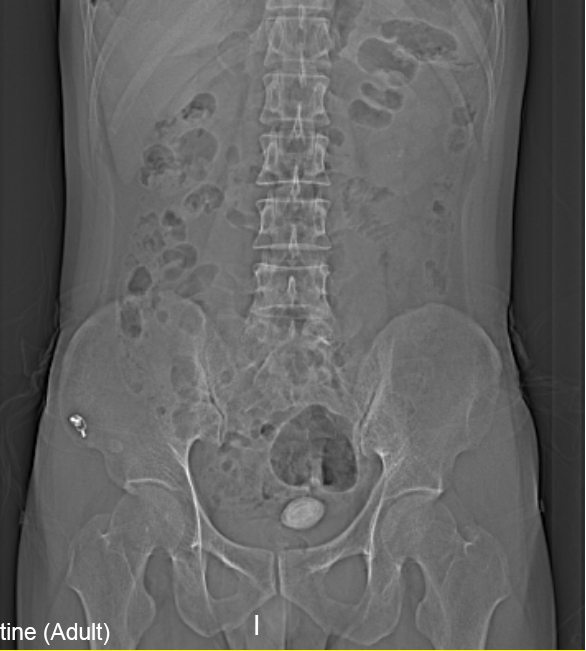

“醫(yī)生我尿不出,尿里有血,快幫幫我”。近日,在溫州市人民醫(yī)院泌尿外科門診一位男青年向坐診的黃來劍主任求助,經(jīng)驗(yàn)豐富的黃主任在了解基本病情后,特意觸摸了一下患者恥骨上區(qū),并囑咐患者進(jìn)行泌尿系平片檢查,結(jié)果在意料之中也出乎意料之外。意料之中的是患者診斷如黃主任所想膀胱結(jié)石進(jìn)入尿道卡住了,意料之外的是結(jié)石直徑達(dá)到了35mm,像蛋黃大小了,這對(duì)年輕患者來說并不常見,堵住了尿道,把患者痛的夠嗆。

▲患者影像學(xué)檢查